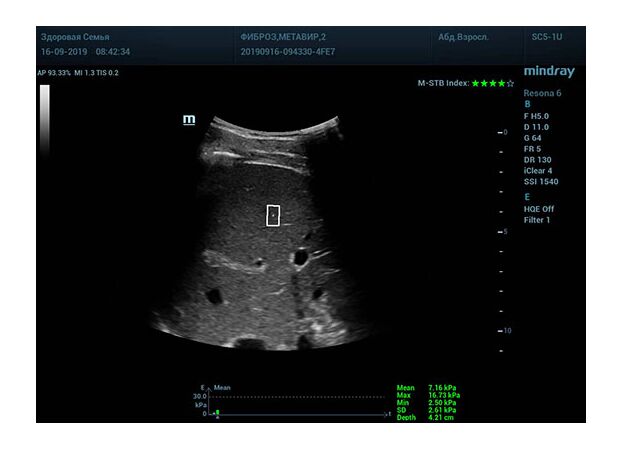

Определение плотности печени. Не ошибся ли оператор при измерении эластических свойств печени? Для оценки критериев качества предусмотрен индекс MBT, который покажет насколько «твердой» была рука оператора и двигалась ли печень. При MBT 5* рука тверда и показатели достоверны. Для оценки качества результатов используется IQR индекс, отображающий колебания показателей в точке измерения при расчете медианы. Показатели при IQR <30% считаются приемлемыми. Техника сканирования через межреберные промежутки требует размещение окна интереса на несколько сантиметром ниже капсулы, для исключения эффекта реверберации. Установка ROI на паренхиму без захвата сосудов, для исключения погрешностей измерения.

Стадия фиброза определяется по системе METAVIR Staging, построенной на данных биопсии и сопоставлении с данными эластографии. Своевременная диагностика фиброза, и начало его лечения, залог благоприятного исхода заболевания.

• METAVIRF0 – норма.

• METAVIRF1 – Портальный фиброз без вовлечения перегородок

• METAVIRF2 – Портальный фиброз с вовлечением нескольких перегородок

• METAVIRF3 – Портальный фиброз с вовлечением множества перегородок

• METAVIRF4 – Цирроз.